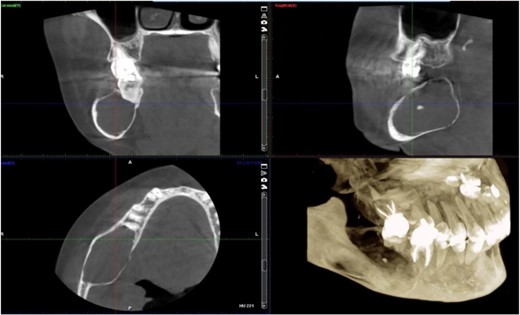

A 40-year-old woman presented with swelling on the right side of her mandible. She had completed orthodontic treatment 2 years earlier. A panoramic radiograph showed a unilocular radiolucency extending from the mandibular angle to the right first molar region (Figs 1–3).

Panoramic radiograph showing a unilocular radiolucency extending from the right mandibular angle to the right first molar region.

Panoramic radiograph highlighting the extent of the lesion from the mandibular angle to tooth #46.